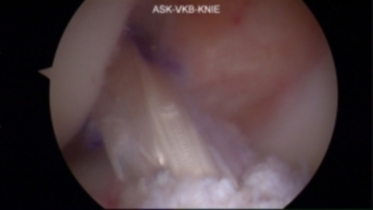

Kreuzbandersatz

Mit 80.000 Verletzungen pro Jahr in Deutschland stellt die Ruptur des vorderen Kreuzbandes eine typische und häufige Verletzung des Sportlers dar. In den vergangenen Jahren hat sich durch die Weiterentwicklung arthroskopischer Techniken die operative Behandlung von Kreuzbandrissen erheblich verbessert. Besonders hervorzuheben sind hier insbesondere das bessere kosmetische Ergebnis, kürzere Operationszeiten und Klinikaufenthalte, weniger Schmerzen und eine geringere Belastung für die Weichteile des Knies.

Als Standard hat sich im deutschsprachigen Raum durchgesetzt, körpereigene Sehnen als Transplantat zu entnehmen. Hier stehen neben den häufig verwendeten „Hamstring“-Sehnen (Semitendinosus- und Gracilis-Sehne) Transplantate aus der Patellarsehne sowie der Quadrizepssehne zur Verfügung.

Die Rehabilitation beginnt während des stationären Aufenthaltes und beinhaltet nur noch in Einzelfällen die Versorgung mit einer gelenkstabilisierenden Orthese. Das standardisierte Nachbehandlungsschema kann durch den Operateur angepasst werden, wenn z.B. Begleitverletzungen vorliegen. Bei optimaler Nachbehandlung kann man mit einer Normalisierung der Funktion nach sechs bis neun Monaten rechnen.